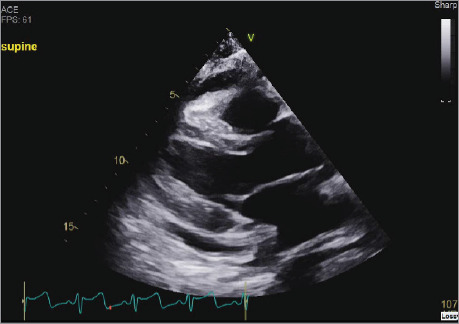

食管心包瘘是一种极为罕见的结构缺陷,可能由恶性或医源性病因引起。本文报告一例食道心包瘘致心包积液并发心包填塞的病例。鉴于这种疾病的高发病率和死亡率,本文描述了在诊断和临床决策方面的挑战,以提高早期识别和跨学科管理。

Esophagopericardial fistulas are an extremely rare structural defect that may arise from malignant or iatrogenic etiologies. This article reports the case of a patient with cardiac tamponade secondary to hydropneumopericardium from esophagopericardial fistula. Given the high morbidity and mortality of this condition, this article describes challenges in diagnosis and clinical decision-making to improve early identification and interdisciplinary management.